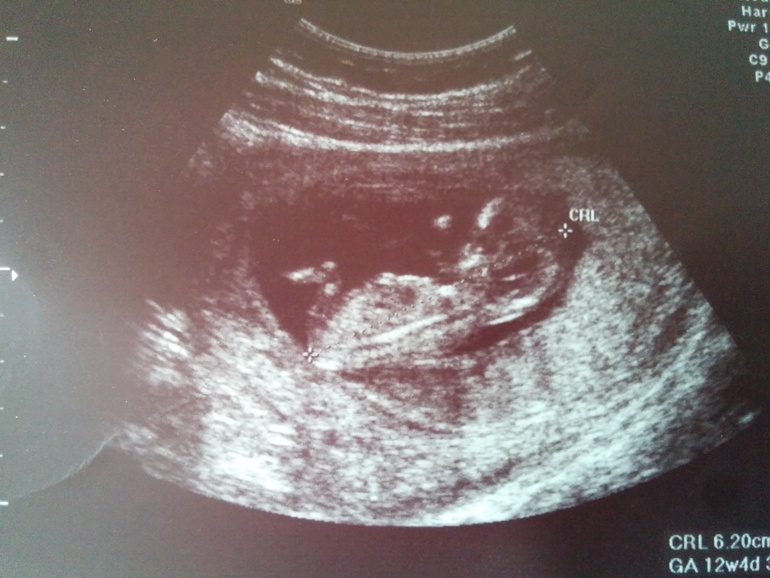

скрининг 1 триместра - мой крохотунчик дрыгается))

Наш тоже вертелся не давал тете врачу измерить)))) Слава богу все хорошо, теперь жду результаты крови. А вот показатели:КТР 56БПР 19ТВП 1,0НК 2,1